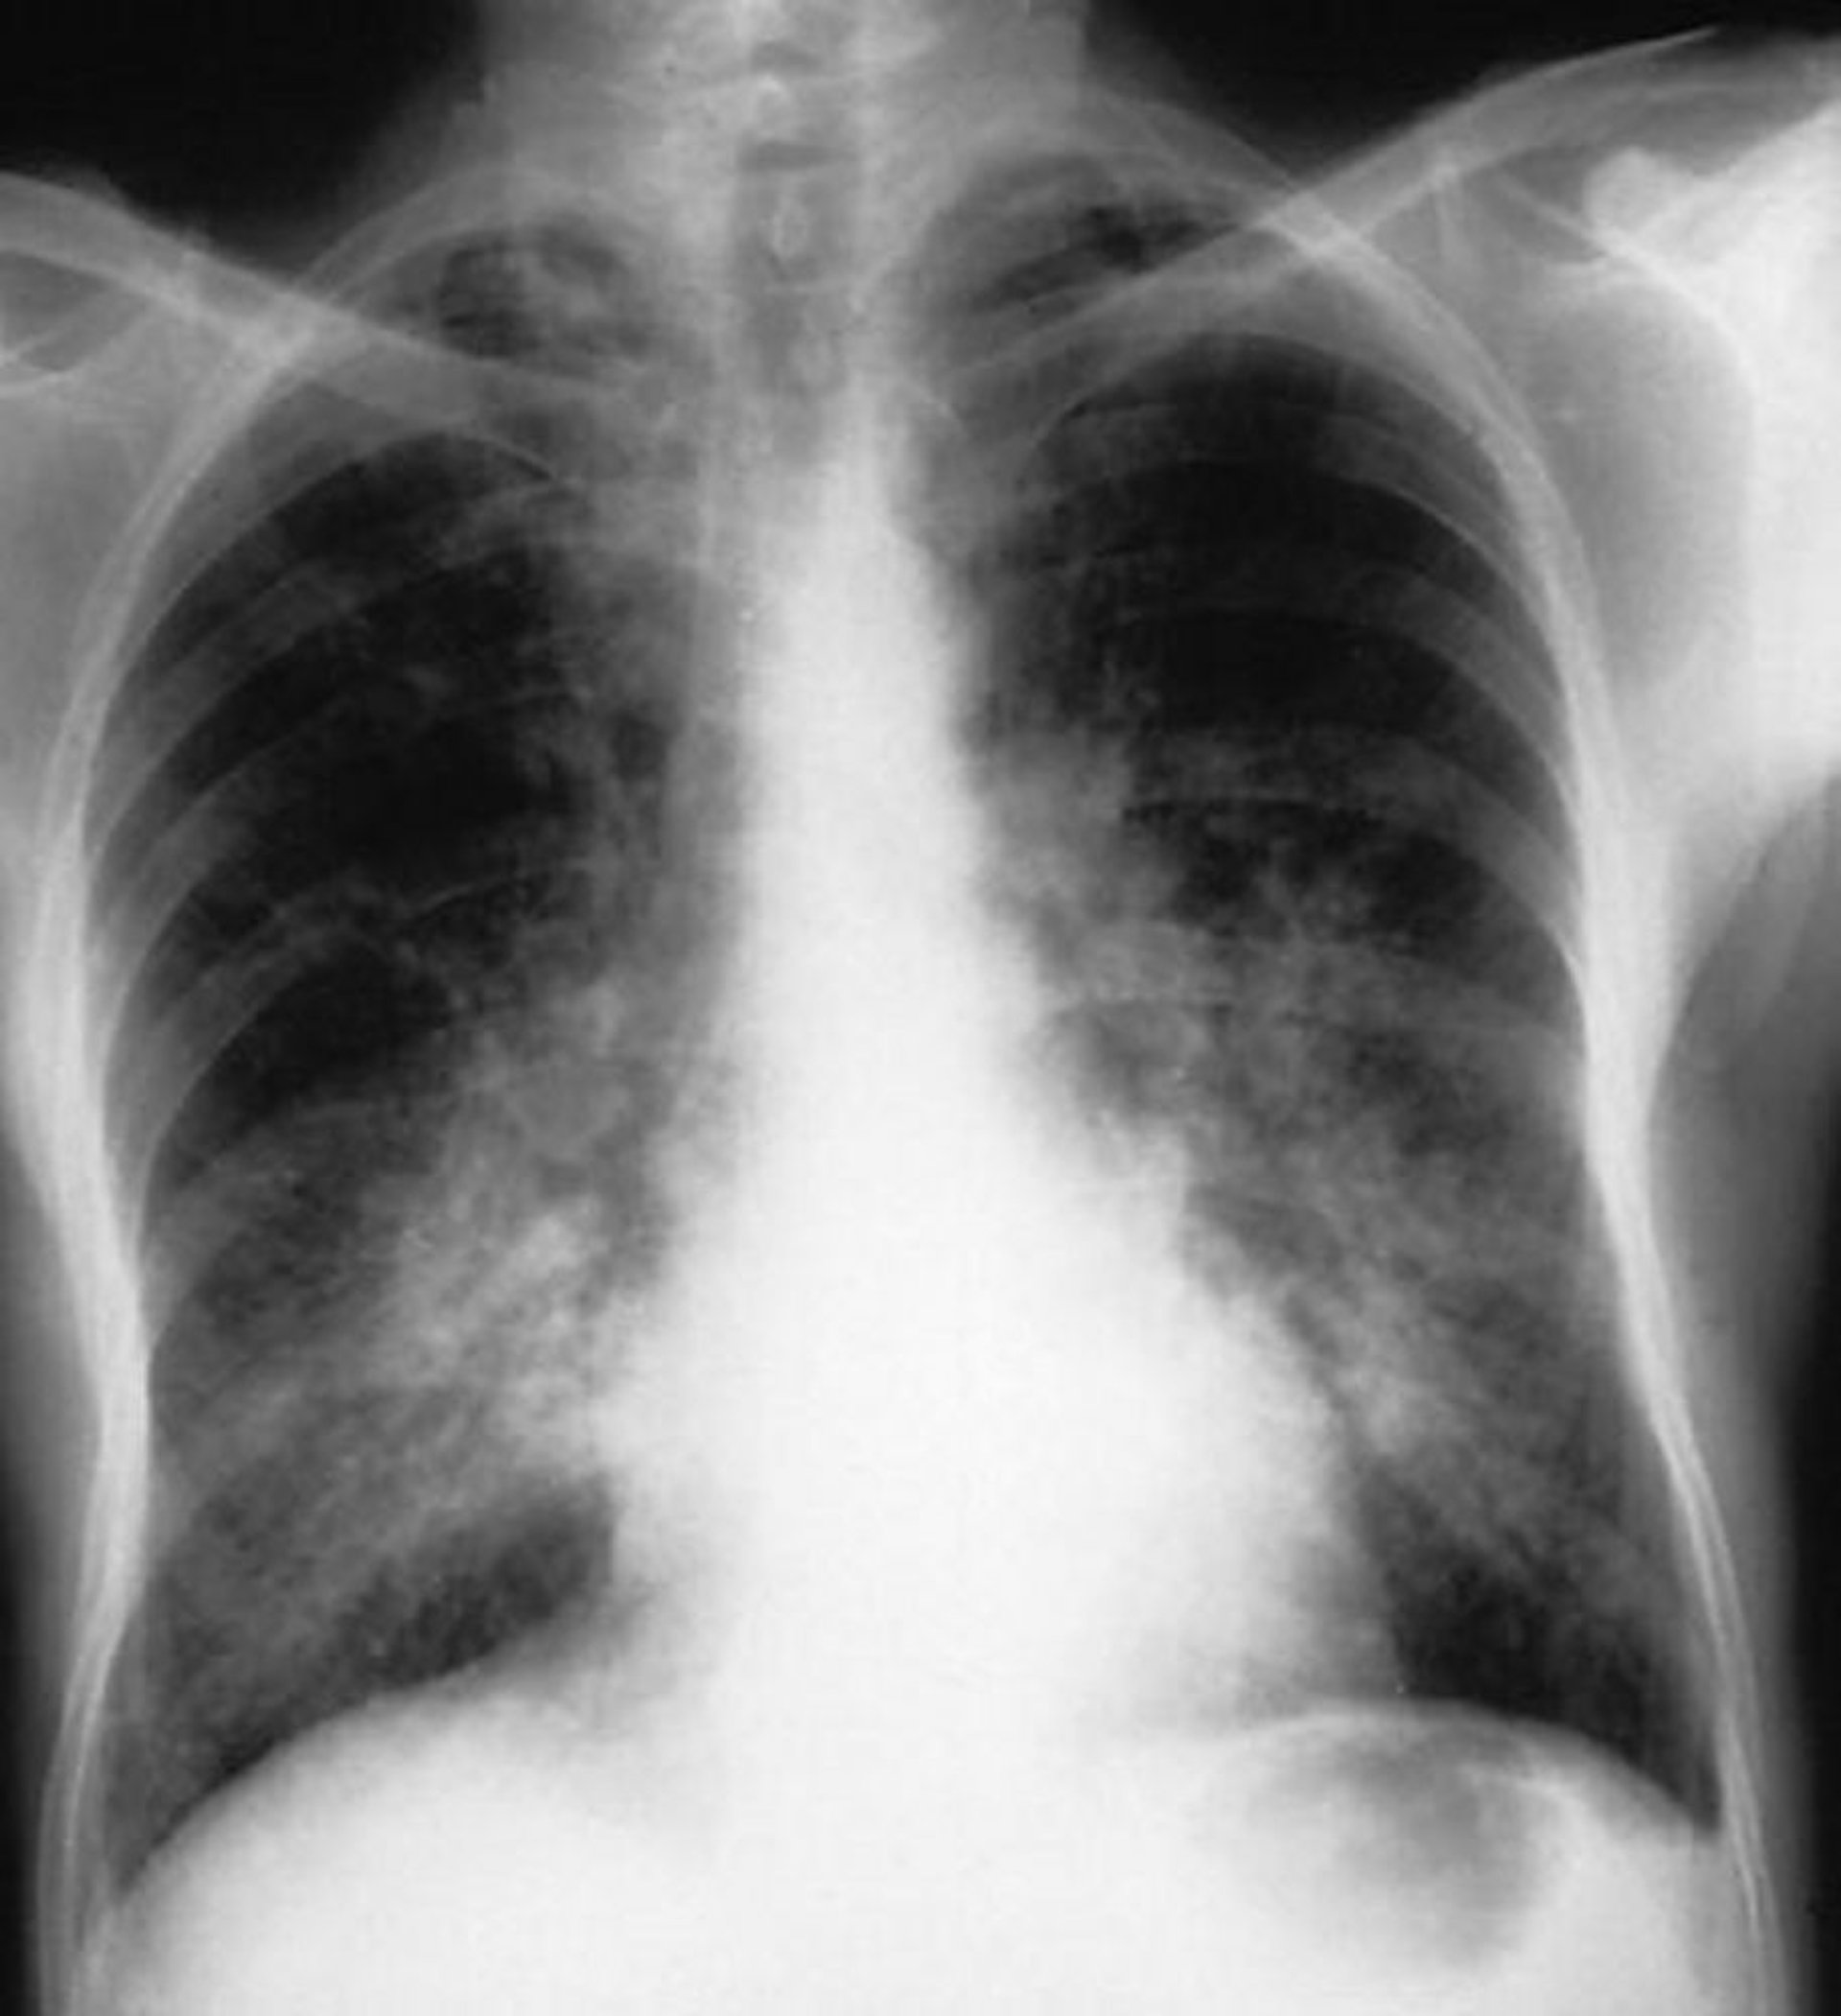

Emorragia alveolare (sindrome di Goodpasture)

Opacità alveolari bilaterali in un paziente con emorragia alveolare causata dalla sindrome di Goodpasture.

By permission of the publisher. From Cohen A, Glassock R. In Atlas of Diseases of the Kidney: Glomerulonephritis and Vasculitis. Edited by R Schrier (series editor), RJ Glassock, and AH Cohen. Philadelphia, Current Medicine, 1999.